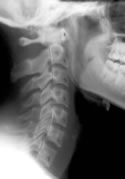

Identifying these ligamentous injuries, however, can be difficult. The ligaments themselves may be detected on MRI, but they cannot be seen on normal radiographs. It is more likely that the ligament injury will result in changes to the alignment of the cervical spine, and that can be detected with plain films.

A 2002 study1 compared the angle of cervical lordosis between whiplash patients and healthy controls. They found a statistically significant difference between the two groups, suggesting that whiplash injuries may indeed alter cervical spine alignment.

Now, a new study2 has shown that chiropractic treatment can improve cervical lordosis in patients after a motor vehicle collision.

After a period of care, neutral radiographs were again taken, and both the pre- and post-treatment films were evaluated by a second chiropractor who was blinded to which films belonged to which patient.

The cervical curve was measured in each of the x-rays.

10 of the 13 patients showed an increase in the cervical lordosis found on x-ray. The average increase found in the patients was 6.4°.

One patient showed no change and two patients showed a decrease in cervical lordosis.

This study suggests that chiropractic adjustments do indeed increase cervical lordosis, which may be helpful for patients suffering from auto injuries. The sample size in this study was small, and the authors stress the need for further study into this matter.